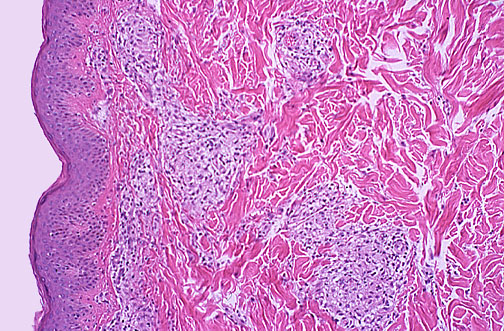

| Hansen's disease, also known commonly as leprosy, is the result of infection with Mycobacterium leprae. This infectious agent is poorly transmissible, and years of close contact with an infected person are necessary to acquire leprosy. This disease is still endemic in economically disadvantaged areas in tropical climates. Depending upon whether cell-mediated immunity is good or bad, infected patients may exhibit a "tuberculoid" or "lepromatous" form of disease respectively, depending upon whether there is a predominantly TH1 or TH2 cell mediated immune response. Seen here in dermis are ill-defined granulomas with an appearance that is "borderline" or between tuberculoid and lepromatous. |